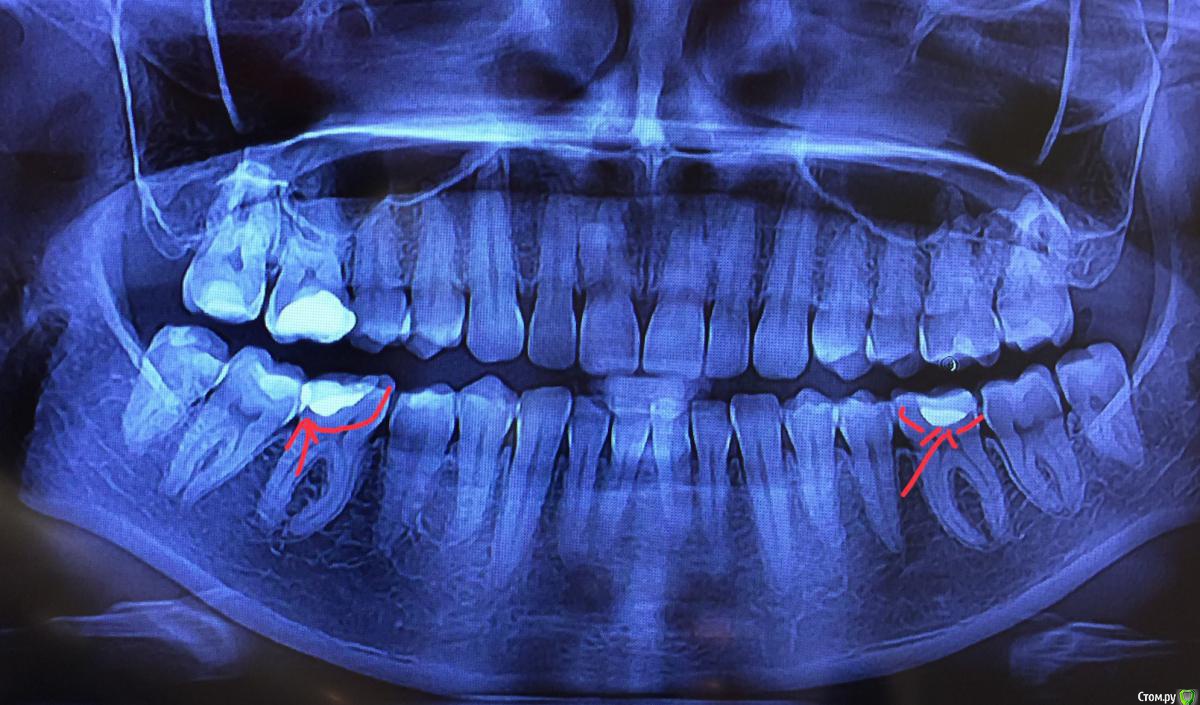

viktoria.v Опубликовано 31 мая, 2019 Поделиться Опубликовано 31 мая, 2019 Добрый день! У меня вопрос по наличию кариеса на снимке. Пол года назад заменила пломбы на всех зубах. Сегодня была на плановой чистке (в другой клинике) попросила сделать рентген, чтобы убедиться, что все в порядке. Доктор сказал заменить нижние пломбы, показал на снимке темные области между пломбой и зубом. Это действительно кариес? Если да, в следствии чего он мог так быстро образоваться? Ссылка на комментарий